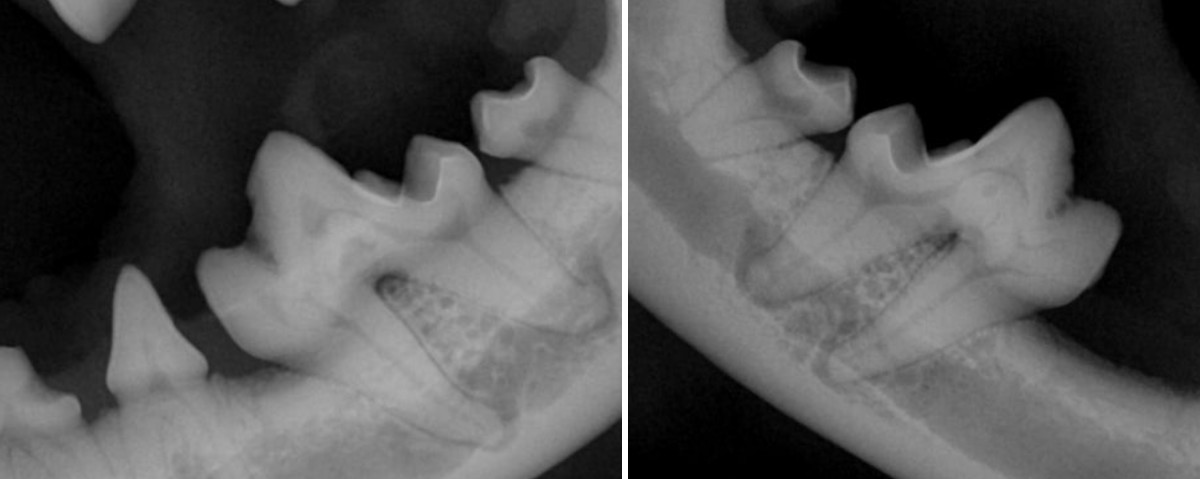

그러나 방사선 촬영을 해보면 치수관이 정상적으로 이어지지 않고 끊긴 음영 이중 구조처럼 보이는 치근 내부 형태 세균 침투 통로가 형성된 공간 이 확인됩니다.

방사선 촬영 결과

양측 상악 제1대구치(M1)에서 치내치 전형적 소견이 확인되었습니다.

이미 치조골 소실이 동반되어 있었고 치아 기능 유지가 어려운 상태였습니다.